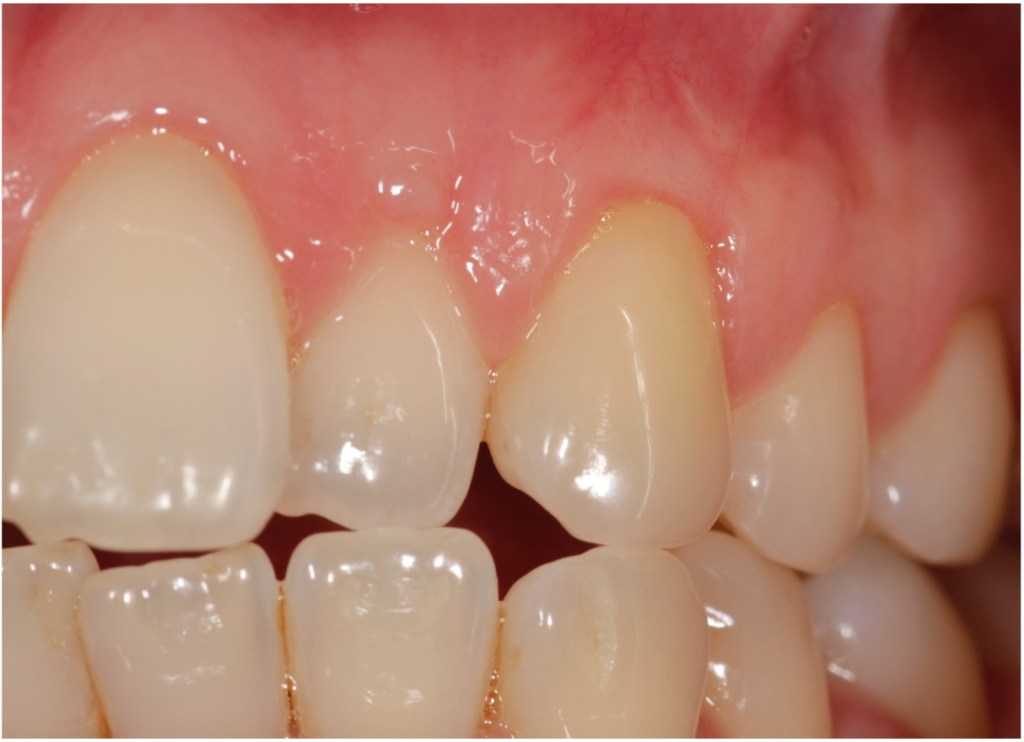

Recession surgery – connective tissue graft

A connective tissue graft is another way to cover recession. This takes a sub-layer of tissue from the palate. The advantage of this is more comfortable healing from the palate and a better colour match to the grafted area.